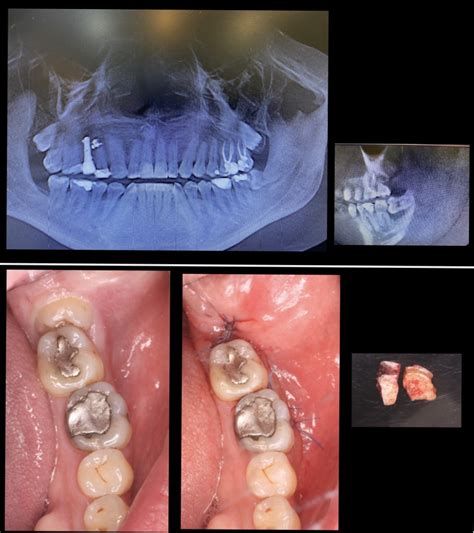

Las muelas del juicio, también conocidas como cordales, generalmente erupcionan entre la adolescencia y la adultez. Su anatomía puede variar, presentando entre uno y seis conductos y de una a cuatro raíces. Es importante destacar que no siempre es necesario extraer las cordales, lo cual debe ser evaluado por un profesional mediante una radiografía.

Como ya se mencionó, la extracción de las muelas del juicio no siempre es necesaria. Sin embargo, si un profesional determina que es requerida y no se realiza a tiempo, pueden surgir riesgos y afecciones como:

- Caries: Debido a la dificultad de limpieza cuando la muela no puede salir del todo.